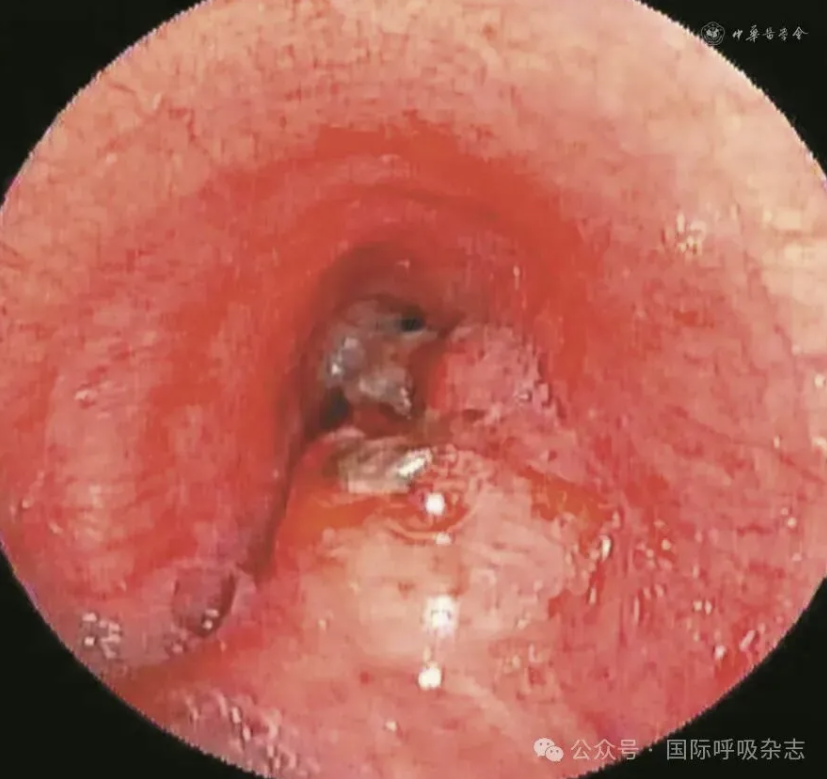

患者男,61岁,因“食管癌术后3年,咳嗽、气喘半年”于2025年3月14日入院。患者于2022年确诊食管鳞癌,曾接受新辅助免疫联合化疗、食管癌根治术、术后辅助免疫治疗、局部放疗及多线化疗等规范治疗。2024年12月经胃镜检查确诊为“气管食管瘘”,遂行空肠营养管置入术(图1)。后因咳嗽、气喘症状持续,辗转多家医院治疗效果不佳就诊于西安市胸科医院。入院查体:端坐呼吸,声音嘶哑,双肺可闻及湿性啰音及喘鸣音。实验室检查示炎症指标升高:白细胞计数8.82×109/L,中性粒细胞比例88.8%,C反应蛋白165.88 mg/L。血气分析pH值7.435,PaCO2为45.2 mmHg(1 mmHg=0.133 kPa),PaO2为55 mmHg,氧合指数200 mmHg,提示Ⅰ型呼吸衰竭。胸部CT提示气管食管瘘,伴双下肺感染及实变(图2)。支气管镜下见气管中下段膜部菜花样新生物,新生物下方可见瘘口(图3)。

图3:61岁男性气管食管瘘患者支气管镜检查(2025年3月15日)示气管中下段膜部可见菜花样新生物,于新生物下方可见气泡冒出,考虑瘘口形成

经院内多学科诊疗(胸外科、肿瘤科、影像科、消化科等),确定行气道支架置入术治疗气管食管瘘,其中气道支架的大小及种类选择决定手术成败。通过气道三维重建(气管上中段管腔狭窄,长度约45 mm,狭窄上端距声门下约58 mm,狭窄下端距隆突约28 mm,最窄内径约12.8 mm×3 mm;气管上段距声门下腔约82 mm处可见管壁破损,与食管相通,瘘口宽约2~3 mm)(图4)及多次支气管镜下的测量数据,最终确定气道支架型号为:金属覆膜20 mm×60 mm。2025年3月17日行气管新生物电凝圈套切除及消融治疗(图5)。2025年3月20日在全身麻醉硬质支气管镜下成功置入气道金属覆膜支架(图6),术后患者呛咳症状即刻缓解。